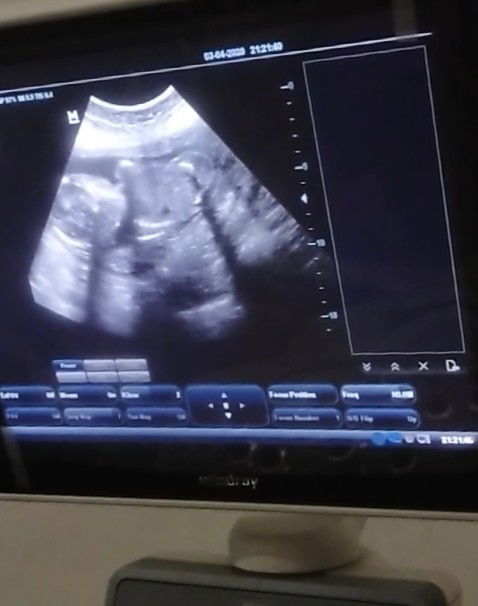

17 Oktober 2019 adalah kejadian memilukan bagi kami anak pertama kami usia kandungan 27 meninggal dalam kandungan karena preklamsia , terdeteksi pada usia kandungan 18 Minggu dengan tensi 150/100 - 170/100 segala upaya kami lakukan Konsul ke beberapa dokter dan minum suplemen, pola hidup sehat tapi hasil tekanan darah tidak kunjung turun. . Kini istri saya hamil lagi usia kandungan 19 Minggu dan preklamsia datang lagi, ya Allah cobaan apalagi ini sedih saya melihat tekanan darah istri 170/100, rasa kekhawatiran muncul lagi jujur saya takut sekali kehilangan seperti yang pertama Segala upaya sudah saya lakukan namun dokter pun bilang susah untuk mengobati preklamsia, walaupun dengan obat hanya turun sedikit tekanan darahnya atau dalam kata lain gak ada obat nya. Konsul ke beberapa dokter jawab nya sama obat tidak bisa membantu, hanya ada 1 cara mempercepat kelahiran dengan cara operasi Caesar itu nunggu hingga kandungan 33-35 Minggu Kenapa mesti ada preklamsia di bumi ya Allah, preklamsia dapat mengacam istri dan calon bayi saya. Yang Allah kuatkan istri hamba dan sehatkan anak hamba agar lahir dengan selamat Permudah istri saya untuk mengandung calon bayi hambah Berilah hambah kepercayaan untuk memiliki keturunan Mohon doa keselamatan untuk istri saya dan calon bayi saya teman #theasiaparents Mungkin ada yang punya solusi Sulaiman & septiliana Terimakasih